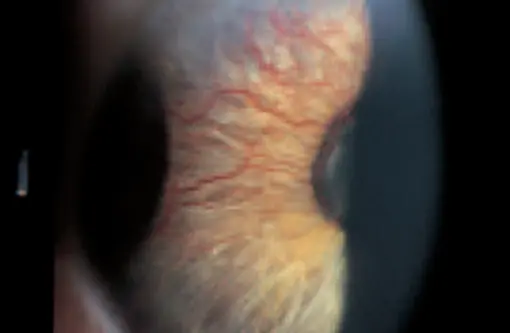

Hyphema (Blood in the anterior chamber) Z

Causes: resulting to blood in anterior chamber

- Trauma

- Rupture of abnormal iris vessels

(NEVER select HYPERTENSION)

Complications:

- Secondary glaucoma with elevated IOP

- Recurrent bleeding

- Corneal blood staining

- least common is corneal fistula

Treatment:

Hospital admission

Semi-sitting position & Rest

Promote blood resorption

Antiglaucomatous eye drops treatment for elevated IOP

Follow up with the patient with level of Hyphema and IOP

Surgery indicated only in (if total/subtotal Hyphema, resistance treatment, persistent IOP) - aspiration of blood from anterior chamber and glaucoma surgery

Avoid aspirin or any drugs that increase bleeding